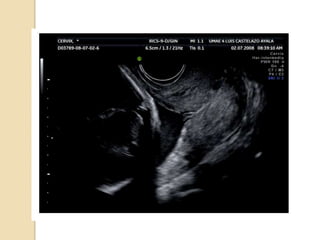

◦ Dx USG:

 OCI 15mm 1er trimestre

 20mm 2º trimestre

DIAGNÓSTICO  Embarazo: ◦ Sospechaclínica en pacientes con antecedentes pérdidas ◦ Dx USG:  OCI 15mm 1er trimestre  20mm 2º trimestre